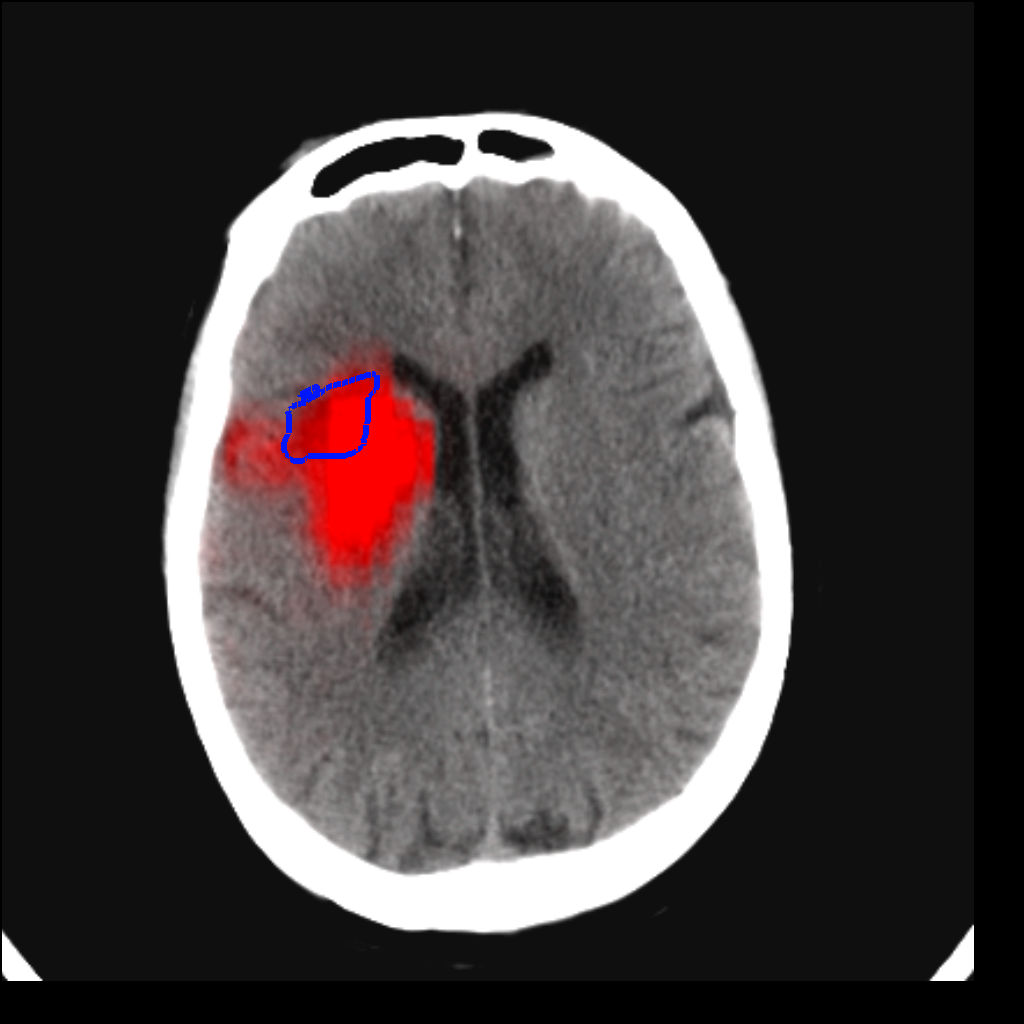

Fig. 3 shows a scatter plot and a Bland-Altman plot of the true and predicted volumes for all subjects in the testing folds using the proposed method. The mean volume error is -2.8 ml (the prediction is a slight underestimation) and the mean absolute volume error is 36.7 ml. The mean Dice score is 0.48. A representative set of predictions is shown in Fig. 4.